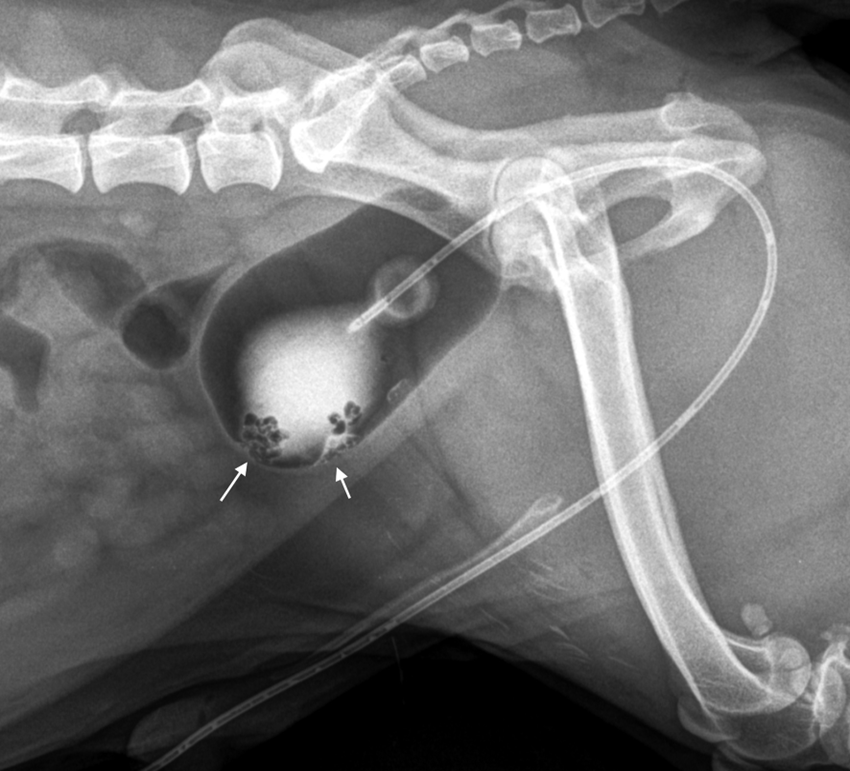

What is the double contrast cystography showing here?

Growth of polyps from bladder wall —> polypoid cystitis

Soft tissue of polyps outlined by contrast

Using folley urinary catheter —> has balloon on end, stops catheter dislodging from UT —> gets stuck @ neck of bladder